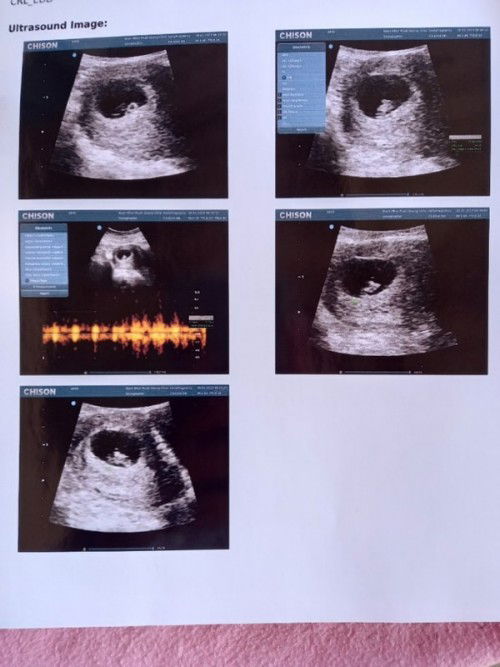

พอดีเรามีเลือดออกเลยไป รพ อายุครรภ์6week 6day โดยประมาณ ได้ซาวผ่านช่องคลอดดูถุงอยู่ในมดลูกถุงสวยดูปกติดีแต่ไม่เจอตัวเด็กหมอบอกน้องอาจะยังเล็กอีกอาทิตย์ให้มาซาวใหม่แอบกังวลค่ะแท้งมา2ท้องติดแล้วกลัวท้องลม🥺 #แม่ๆบ้านไหนมีภาพซาวด์ตอน6วีคมาแบ่งปันกันได้นะคะ อัพเดตค่ะ26/01/2023 เจอน้องแล้วค่ะอายุครรภ์7วีค1วัน อายุครรภ์ไม่ตรงกับประจำเดือนห่างกัน1สัปดาห์ค่ะ ได้ยินเสียงหัวใจแล้วค่ะดีใจมากๆ🥰 #แนบรูปให้อยู่ในภาพที่2นะคะ